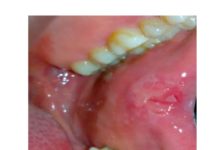

Il lavoro sinergico delle università in oggetto ha mostrato che i pazienti affetti da SIOD con mutazioni SMARCAL1 bi-alleliche nel 66,0% presentava anomalie dentali. Il 46,8% aveva microdonzia e il 52,3% aveva ipodonzia. Il numero di denti mancanti variava da 0 a 15, i premolari erano gli elementi più frequentemente assenti. Oltre ai denti piccoli o assenti, il 72,0% dei pazienti con SIOD presentava radici dei molari ipoplasiche. La sproporzione tra la corona del molare e le radici variava da quasi normale a grave. I premolari permanenti e i primi molari sono prevalentemente malformati, mentre gli incisivi e i canini di solito risultano nella norma.

La maggior parte dei denti presenta una colorazione nella norma tranne in alcuni casi in cui si evidenziano delle opacità.

Come suggerito da Fonseca (2000), il fenotipo dentale in SIOD assomiglia a quello della dentinogenesi imperfetta (DI) di tipo II, che è caratterizzato da denti opalescenti o traslucidi con alterazione cromatica, superficie abrasa, radici corte ristrette e obliterazione delle camere pulpari (Shields et al, 1973). Inoltre, come la SIOD, il tipo DI II interessa sia la dentizione decidua che quella permanente (Sclare, 1948). Tuttavia, a differenza del tipo DI II, i denti SIOD presentano raramente decolorazione, ipoplasia dello smalto e dentina morbida. I denti di tutti i pazienti SIOD oggetto della ricerca presentavano una opacità tendenzialmente normale. In base alle nostre attuali conoscenze il fenotipo dentale di SIOD è unico.